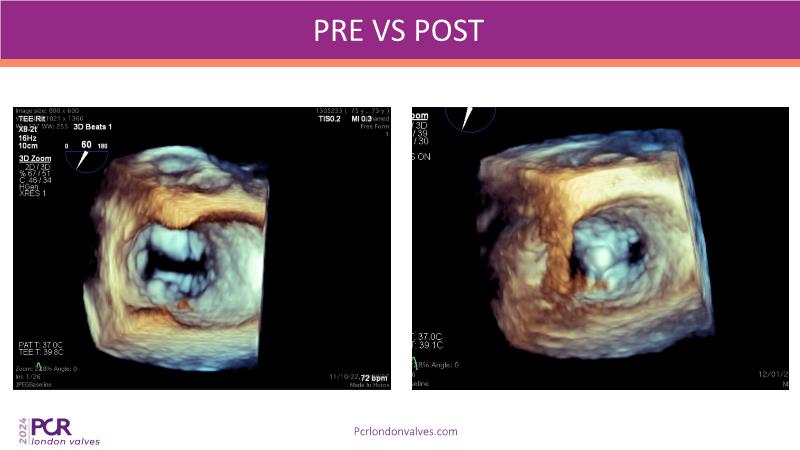

This session on mitral regurgitation offers an in-depth look at the EMPOWER trial outcomes, indirect annuloplasty in aFMR, and remodeling with the CARILLON device. Explore the benefits of early treatment for secondary mitral regurgitation, understand the role of left ventricular reverse remodeling, and review the latest clinical evidence supporting indirect annuloplasty. Discover how this technique keeps future treatment options open while expanding therapeutic possibilities for aFMR.